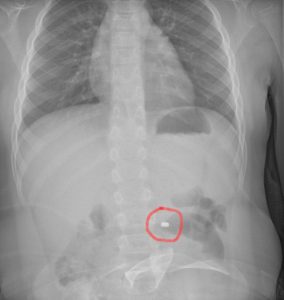

La famiglia, naturalmente spaventata, dopo una prima valutazione al PS della propria città, è stata indirizzata all’Ospedale Cannizzaro di Catania. Qui i medici hanno compreso il pericolo e applicato le linee guida riferite precisamente all’ingestione di una pila a bottone. Eseguita la radiografia dell’addome che ha messo in evidenza la presenza e la localizzazione del corpo estraneo, il bambino è stato condotto in sala operatoria dove gli endoscopisti, con l’assistenza degli anestesisti, hanno potuto estrarre in sicurezza il piccolo oggetto, prima che esso potesse causare conseguenze più importanti. Dopo una notte in osservazione, tornato in piena salute, il bimbo ha fatto rientro a casa con i genitori.